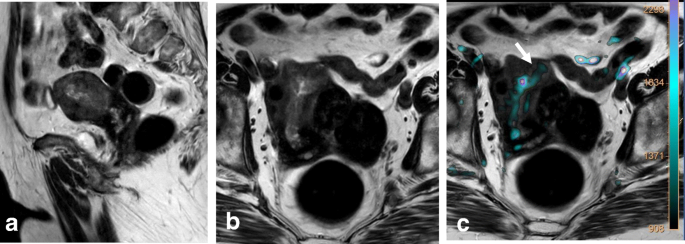

Stage III is now subdivided into three categories. Stage IIIA disease is characterized by involvement of the lower third of the vagina, where the normal hypointense T2W signal of the lower third of the vaginal vault is disrupted by a hyperintense tumor. Stage IIIB tumors exhibit extension to the pelvic wall and/or hydronephrosis or nonfunctioning kidney. Other causes of hydronephrosis (i.e., endometriosis or lithiasis) should be excluded to avoid misdiagnosis of stage IIB disease (Table 6; Fig. 16) [26]. Stage IIIC disease is characterized by the presence of positive adenopathies (FIGO 2018). Stage IIC is further subdivided into IIIC1 (adenopathies located in the pelvis) or IIIC2 (paraaortic adenopathies) (Table 2). When large adenopathies are found, inflammatory and infectious diseases (i.e., tuberculosis and HIV) should be excluded. An accurate clinical history, including all clinical and analytical data, together with fine-needle aspiration or biopsy of the LNs, are critical for establishing a correct diagnosis (Table 6) [26].

MRI reveals FIGO IIIB cervical cancer in a 38-year-old woman with adenomyosis and endometriosis in the left ovary. Visualization by coronal T2WI (a), axial FS T1WI (b), and sagittal T2WI (c) reveals a mass extending to the left parametrium and involving the left ureter (red arrows) below the endometrioma (E), with a subsequent hydronephrosis. d, e DWI (b = 1000/ADC map) reveals diffusion restriction of the cervical mass, with extension to the left ureter. f DCE sequence shows enhancement of the cervical mass and ureter wall